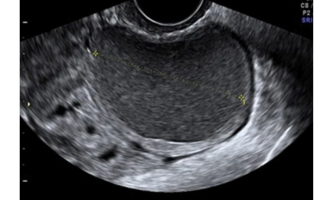

Quiste endometriósico, con parénquima regular en la periferia, denominado “signo de la media luna”, característico de las lesiones benignas. Ausencia de vascularización intralesional (fig2).